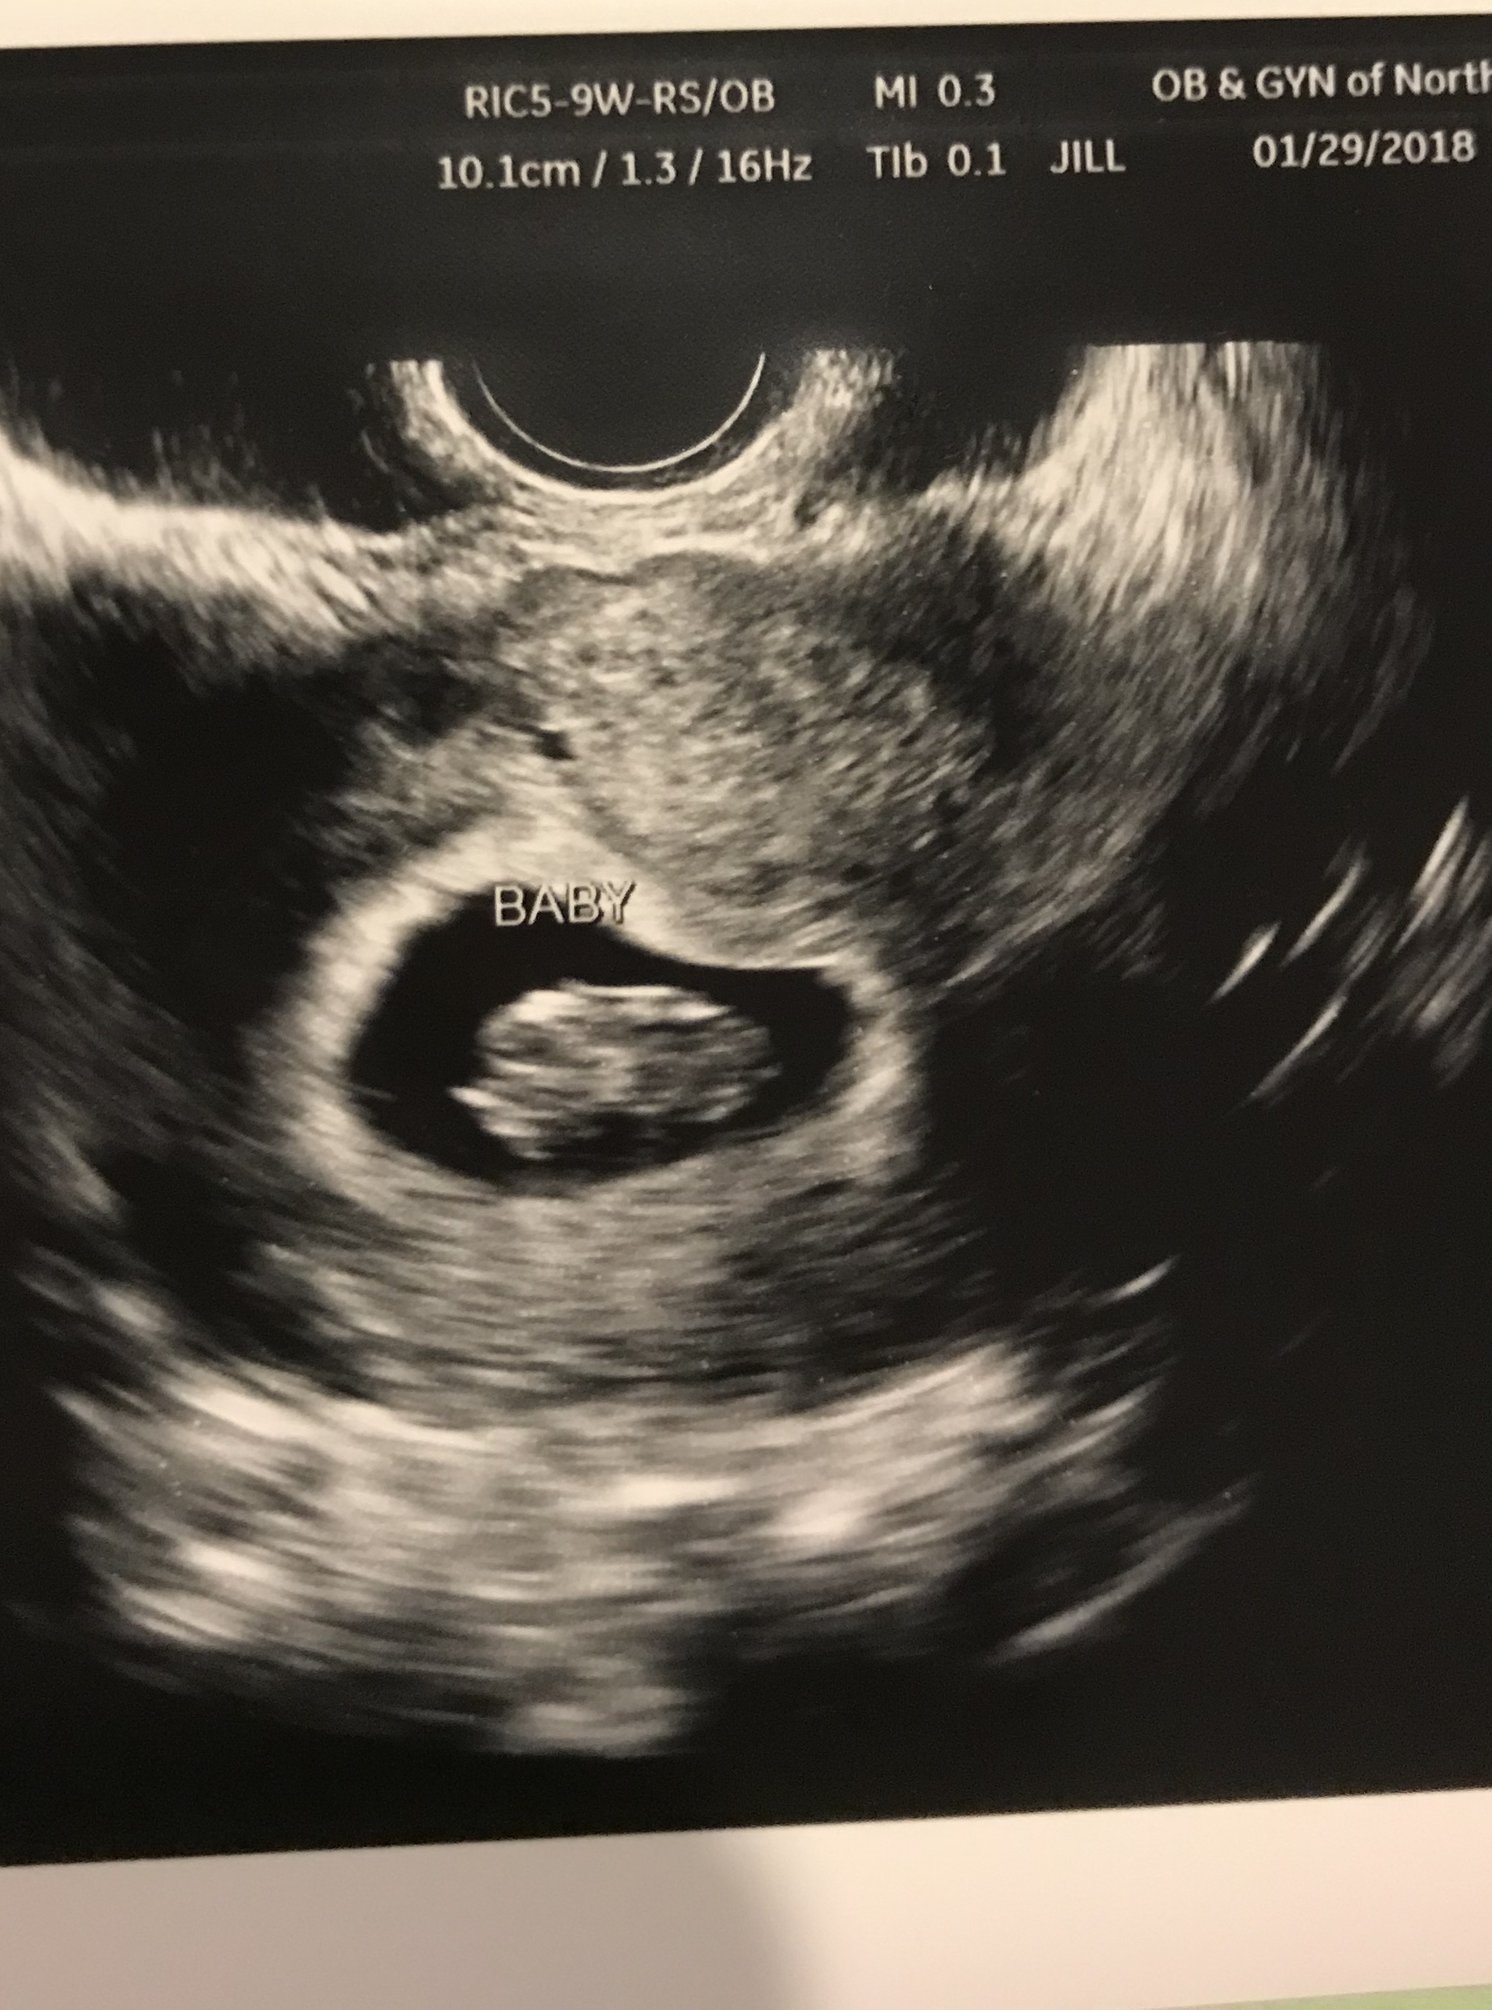

9w0days.. Heart rate is at 169.. Everything looks great. OB told me due to my 2 prev C-Sections, this too will have to be a scheduled C-Section at 39 weeks